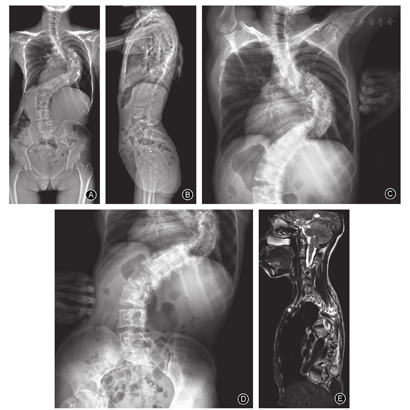

儿童组的主弯Cobb角为31.1°±11.9°(图3)、青少年组为56.7°±17.0°(图4)、成人组为70.7°±22.6°(图5),随着年龄增加,主弯Cobb角明显增大,三组的差异有统计意义(P< 0.001,表2);主弯柔韧性明显降低(63.9%±28.7% vs 43.8%±20.0% vs 36.9±22.7%,P=0.044,表2);次弯Cobb角明显增大(16.8°±8.8° vs 34.8°±14.7° vs 41.6°±17.2°,P< 0.001,表2)。

本研究是首个关于CMI伴脊柱侧凸患者自然史的横断研究,比较儿童组(图2)、青少年组(图3)和成人组(图4)三个不同年龄段患者的影像学特征。结果显示三组患者的非典型弯发生率较高,且各组间弯型分布的差异无统计学意义,这与既往文献报道的结果一致[11,25];随着年龄的增长,患者主弯和次弯Cobb角增大,而主弯柔韧性下降,此结果符合临床经验,与特发性脊柱侧凸相似[26]。此外,有文献报道接受支具或手术治疗的CMI患者,年龄≥10.5岁、Cobb角≥44.5°是侧凸进展的强预测因子[27]。青少年组的CB明显优于另外两组,可能预示着随着年龄增长,CMI患者的冠状面是由失衡到平衡,再到失衡的动态过程,此结果有待于进一步验证。矢状面X线片显示年龄越大的CMI患者,TK、LL、PI和PT均明显增大,这一变化趋势符合正常中国成年人群脊柱和骨盆的矢状面参数[22];CMI患者与正常人群的对比在既往文献中也有报道[28]。